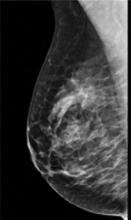

In addition to women with dense breasts, there are also other women for whom mammographic screening is not really enough, which is why research needs to continue in this field. Dr. Wendie Berg, a leading breast cancer specialist, talks with ITN about new research and advancements in breast imaging technology.

Dr. Berg, MD, PhD, FACR, FSBI, is Professor of Radiology at the University of Pittsburgh School of Medicine and Magee-Womens Hospital of UPMC, specializing in breast imaging. She is also the Chief Scientific Advisor to DenseBreast-info.org. A renowned expert, she writes and co-edits one of the leading textbooks on the topic, Diagnostic Imaging: Breast, currently in its third edition, and has co-authored over 120 peer-reviewed research publications.

It has long been said that a national reporting standard is needed in order to ensure all American women receive at least the same basic information regarding breast density, and a spotlight put on the importance of routine breast imaging. Dr. Wendie Berg, a leading breast cancer specialist, shares with ITN what is being done in the fight against breast cancer and the importance of this standardization in reporting for women.